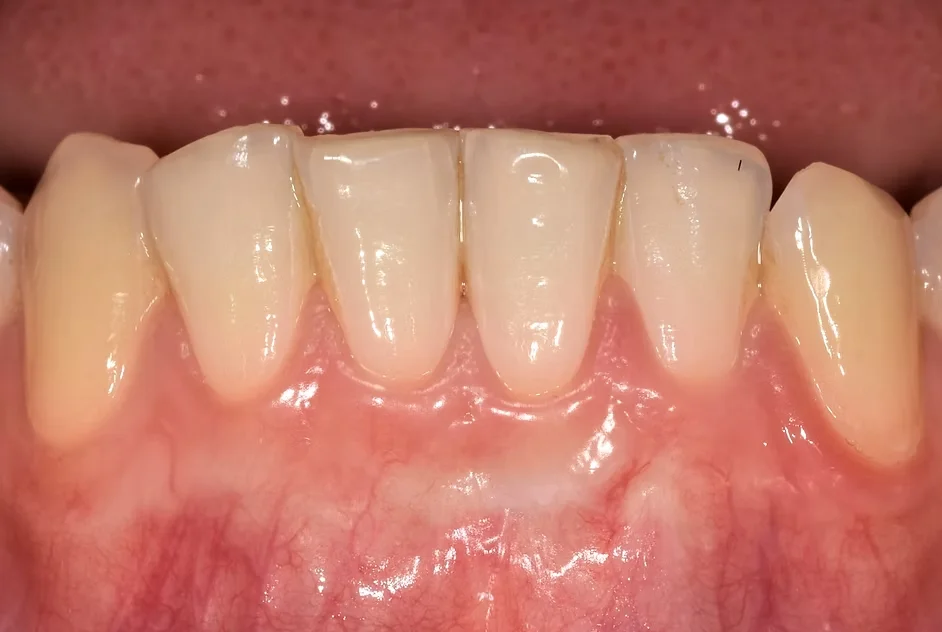

• Gencives rouges, gonflées ou sensibles

• Récession gingivale